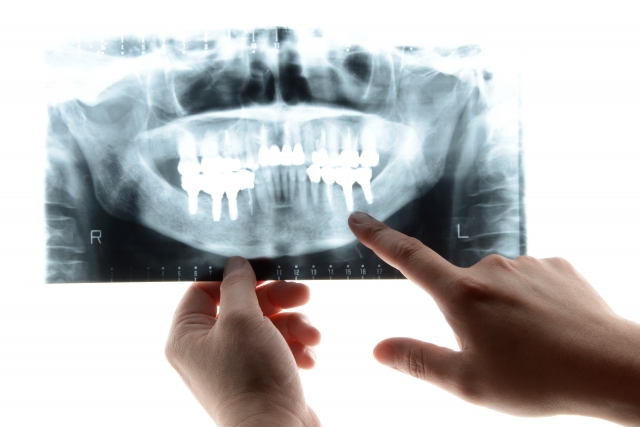

その症状は根尖病変かも?根尖性歯周炎の原因や治療法、歯周病との違いも解説

う蝕(むし歯)の進行段階は?CO〜C4の症状の変化や治療法を解説